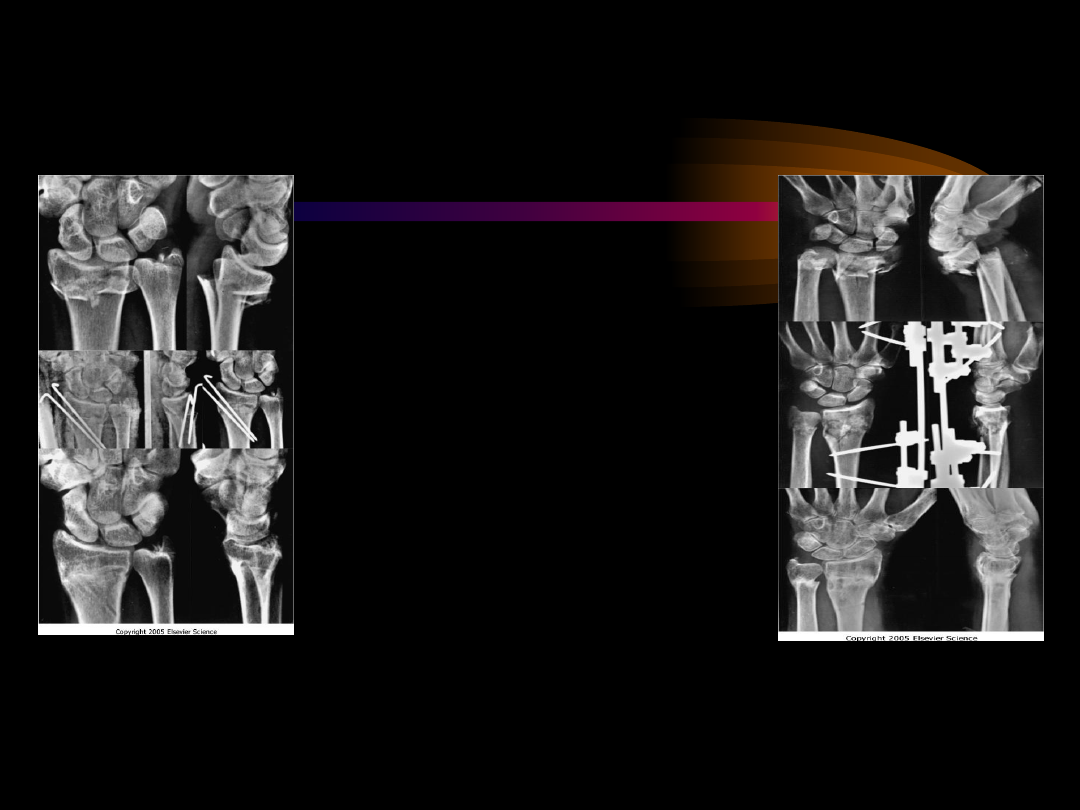

background image

桡骨远端骨折

无移位

移位

可复位

难复位/不稳定

关节外

A2

关节内

B1,C1

A3

闭合复位

部分关节内

B1,B2,B3

完全关节内

C2,C3

经皮穿针或经

皮复位(

C

型臂或腕关

节镜)

随访

继发移位

外固定架,

(±植骨

)或接骨

板固定(

无骨质疏

松)

功能锻炼

切开复位内固

定(螺钉

,支撑接

骨板,克

氏针,张

力带)

有限切开

复位,克

氏针固定

,植骨或

接骨板固

定和植骨

(无骨质

疏松)

石膏托或

管型